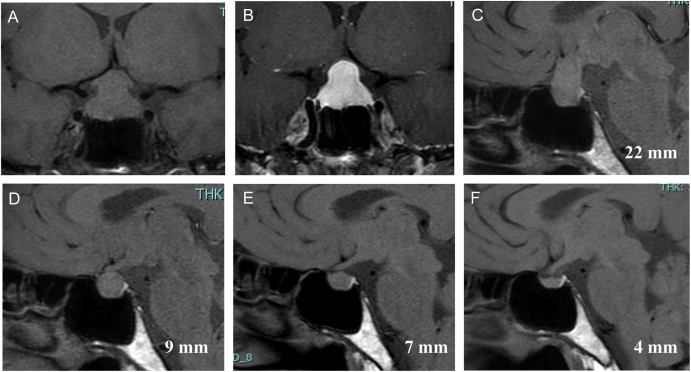

摘要:我们报告一例41岁的日本妇女在怀孕后期视野障碍。在怀孕39周时,她在眼科被诊断为双颞偏盲。核磁共振显示对称垂体增大,压迫视交叉。立即进行了紧急剖宫产手术,生下了一名体重为3112克的男婴。实验室检查显示血清游离甲状腺素(T4)、促甲状腺激素(TSH)、皮质醇、促黄体生成素和促卵泡激素较低。临床诊断为淋巴细胞性垂体炎(LHy)。由于她的视野受损,她每天给予60毫克强的松龙。2天后,她的视野损害迅速改善,导致剂量逐渐减少。治疗开始6个月后,MRI显示脑垂体萎缩。她的强的松剂量减少到每天5mg,并改为每天15mg的氢化可的松。开始治疗12个月后,患者出现甲状腺毒症。检测显示TSH受体抗体阳性,诊断为Graves病(GD)。开始使用噻马唑(每日15mg)和碘化钾(每日76mg)治疗,2个月后甲状腺功能恢复正常。LHy被认为具有自身免疫性机制,并经常与其他自身免疫性疾病相关;然而,GD的发展是罕见的。LHy患者应考虑Graves病的发展,特别是在产后和糖皮质激素治疗过程中。学习要点:患有淋巴细胞性垂体炎的女性在怀孕时经常出现局部症状,如视野障碍。这种情况通常与自身免疫性疾病,特别是自身免疫性甲状腺疾病有关。然而,明确将其与格雷夫斯病联系起来的报道有限。产后时期被认为是格雷夫斯病发病的触发因素。此外,高剂量糖皮质激素治疗及其逐渐减少也可能对其产生影响。

Summary: We report the case of a 41-year-old Japanese woman with visual field disturbances during late pregnancy. At 39 weeks of gestation, she was diagnosed with bitemporal hemianopsia at the ophthalmology department. An MRI revealed a symmetrical pituitary gland enlargement, compressing the optic chiasm. An emergency cesarean section was performed immediately, resulting in the delivery of a male infant weighing 3,112 grams. Laboratory tests indicated low serum free thyroxine (T4), thyroid-stimulating hormone (TSH), cortisol, luteinizing hormone, and follicle-stimulating hormone. The patient was clinically diagnosed with lymphocytic hypophysitis (LHy). Due to her visual field impairment, she was administered 60 mg of prednisolone daily. After 2 days, her visual field impairment improved rapidly, leading to a gradual tapering of the dose. Six months after treatment initiation, an MRI showed shrinkage of the pituitary gland. Her prednisolone dose was reduced to 5 mg daily, and she was switched to hydrocortisone at 15 mg daily. Twelve months after starting treatment, the patient developed thyrotoxicosis. Testing revealed a positive TSH receptor antibody, resulting in a diagnosis of Graves' disease (GD). Treatment with thiamazole (15 mg daily) and potassium iodide (76 mg daily) was initiated, and her thyroid function normalized after 2 months. LHy is believed to have an autoimmune mechanism and is frequently associated with other autoimmune diseases; however, the development of GD is rare. Development of Graves' disease should be considered in patients with LHy, particularly during the postpartum period and the glucocorticoid treatment process.